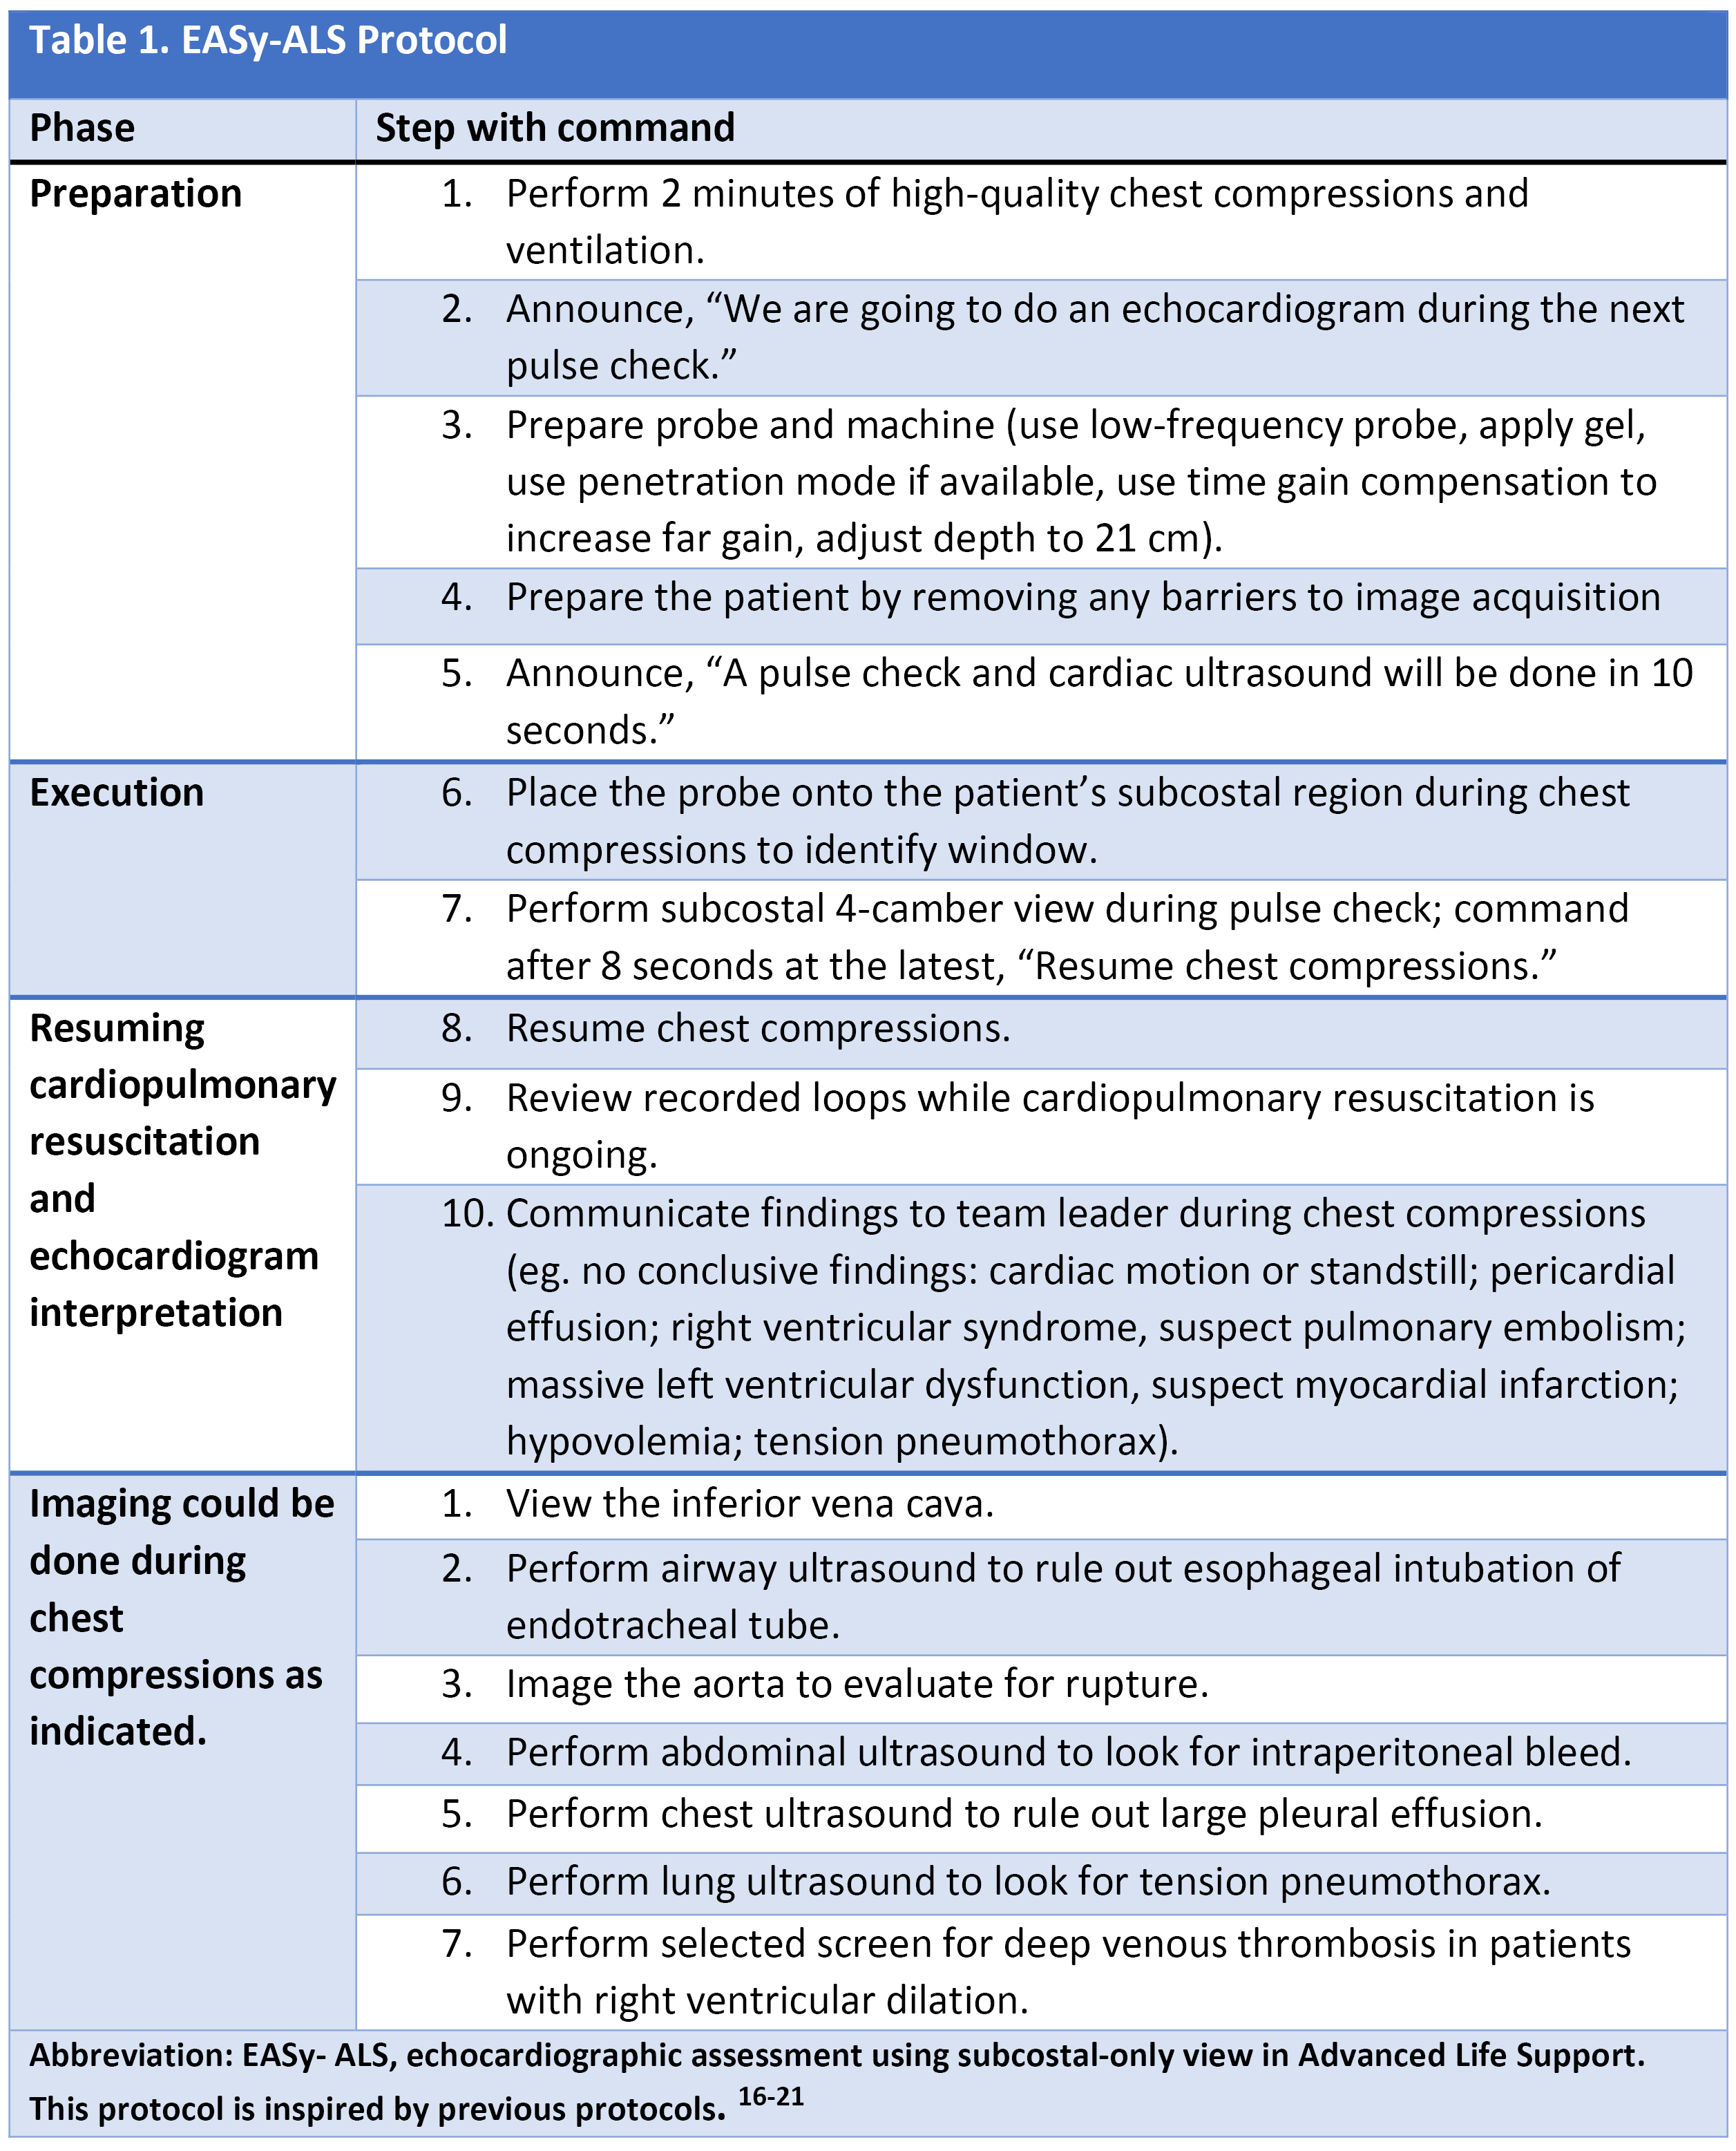

To shorten the duration of interruptions in CPR, protocolized approaches to use ultrasound were developed.15-22 After the introduction of the protocols, the length of CPR interruptions uniformly decreases, although often not to below 10 seconds. With no evidence to support one approach over others, we would like to highlight the EASy-ALS protocol (outlined in Table 1, Figures 1 and 2, and Video 9). The EASy-ALS protocol is the protocol utilized by anesthesiology residents during IHCA.22 This protocol calls for prerequisite training including simulation, which focuses on teamwork, communication, high-quality CPR, and limiting pulse/rhythm checks to fewer than 10 seconds. In our experience, simulation-based training results in consistent shortening of interruptions in CPR during simulated cardiac arrest.23

Table 1. EASy-ALS protocol

Figure 1. Algorithm for the use of EASy-ALS. This algorithm incorporates FOCUS into the ≤10-s pulse/rhythm check of CPR. A systematic approach allows identification of a shockable rhythm if present and completion of EASy-ALS to search for a cardiac cause of the event without holding chest compressions for >10 s. (Used with permission from N. Bughrara, MD, Albany, NY.) CPR indicates cardiopulmonary resuscitation; EASy-ALS, echocardiographic assessment using subcostal-only view in advanced cardiac life support; FOCUS, focused cardiac ultrasound; PEA, pulseless electrical activity; ROSC, return of spontaneous circulation; RWMA, regional wall motion abnormality; VF, ventricular fibrillation; VT, ventricular tachycardia.

The responding resident is alerted to an acutely decompensating patient in the SICU or medical or surgical ward by direct call from the primary service or by overhead Code Blue page. On arrival, the resident prepares to serve as a sonographer and complete an EASy-ALS exam. The ultrasound probe is placed in the subcostal window before the pulse/rhythm check without obstructing chest compressions. The code leader, a senior primary care team provider, is responsible for holding and resuming chest compressions. The code leader assigns a nurse to count down 10 seconds during the pulse/rhythm check; this is standard at our institution. After resumption of chest compressions, the resident interprets recorded images and communicates findings to the code leader. The primary phenotypes (Figure 2) to be identified are cardiac standstill (see Video 1), pericardial effusion (Video 2), dilated right ventricle (RV) (Video 5), dilated left ventricle (LV) (Video 6), and underfilled heart (Video 7). The resident can obtain extracardiac views (such as the subcostal IVC View, Video 3), between pulse/rhythm checks.